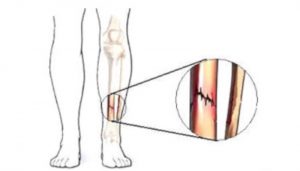

Las fracturas por estrés pueden ocurrir en huesos sometidos a presión constante y repetida, por sobreuso, o micro traumatismos repetidos. Pueden ocurrir en los pies, la rodilla, tibia, peroné, cuello femoral, vértebras, antebrazos etc.